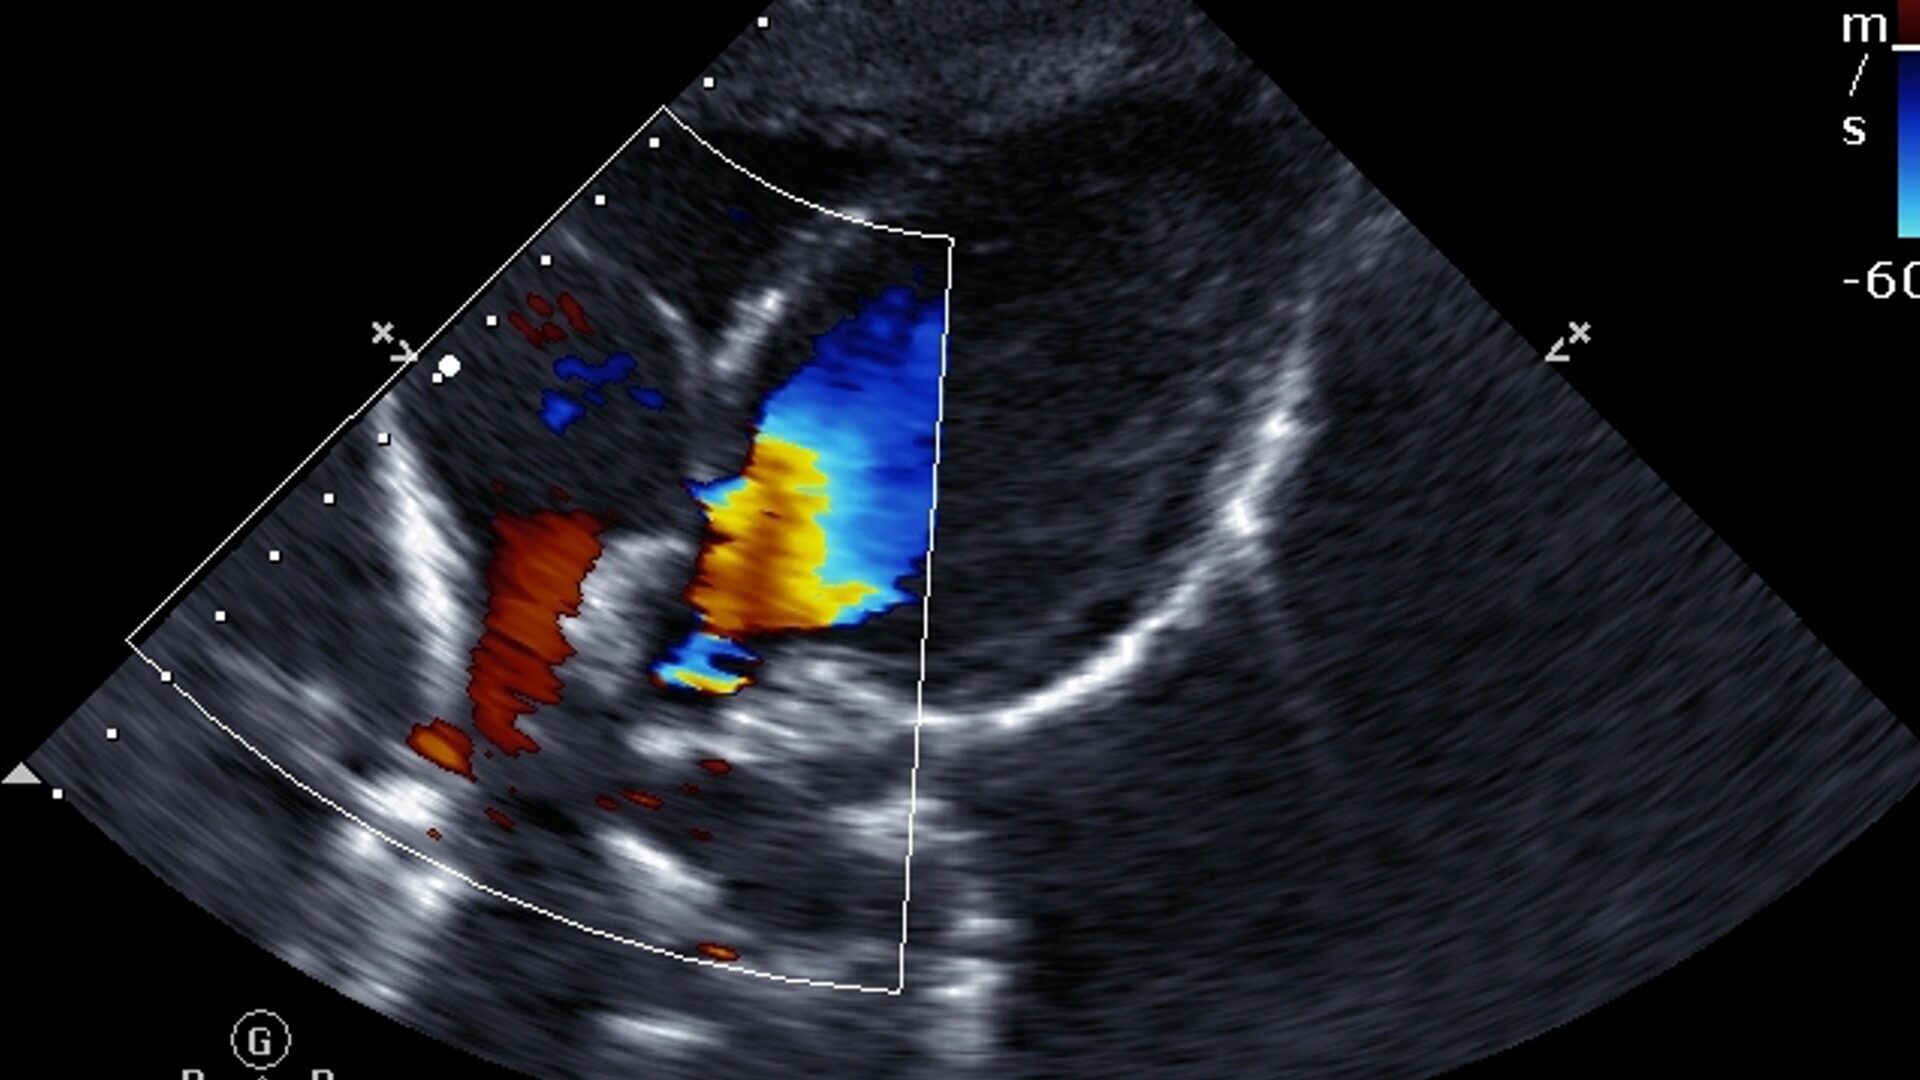

A principal diferença entre o ultrassom convencional e o Doppler está no que eles medem. O ultrassom convencional cria imagens estáticas dos órgãos e tecidos, enquanto o Doppler avalia o fluxo sanguíneo.

Dr. Armênio Mekhitarian, médico radiologista e diretor técnico do Instituto Avançado de Imagem (IAI), explica que o Doppler permite uma visualização mais dinâmica e detalhada do movimento do sangue nos vasos, “o que é fundamental para identificar obstruções, anormalidades e alterações na circulação que poderiam passar despercebidas no exame tradicional“, diz.